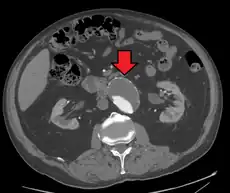

A ruptured AAA with an open arrow marking the aneurysm and the closed arrow marking the free blood in the abdomen -